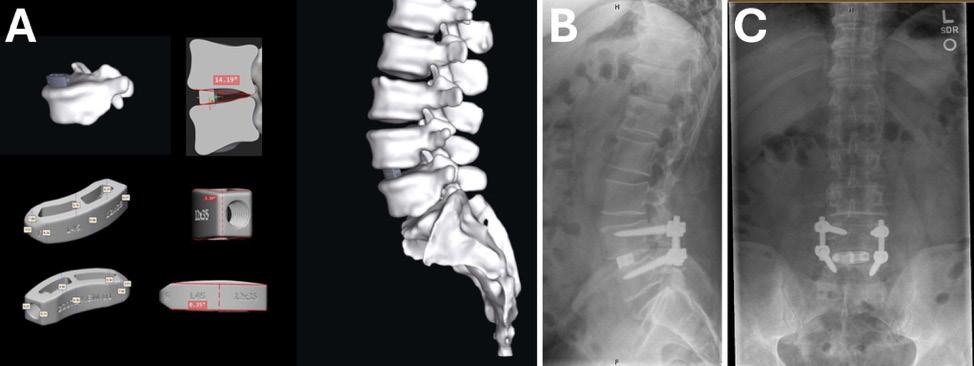

1. A 49-year-old man who had a prior L4-5 microdiscectomy by another provider had L4-5 spondylosis and recurrent disc herniation causing severe central and foraminal stenosis as seen on magnetic resonance images (B and C). Standing scoliosis radiograph (A) demonstrates collapse of the L4-5 disc space with loss of segmental lordosis.

the personalized fit of PSICs can streamline the surgical process. Fewer trials of implant sizes and decreased surgical remodeling of anatomy lead to less time in the operating room and fewer instruments being used and needing sterilization.1 A patient case is highlighted in Figures 1, 2 , and 3

Figure 3. Postoperative sagittal (A) and coronal (B) computed tomography images confirm satisfactory cage placement consistent with preoperative planning.

Figure 2. (A) Design of a personalized interbody cage at L4-5 based on preoperative computed tomography imaging. (B and C) Postoperative radiographs demonstrating ideal cage placement.